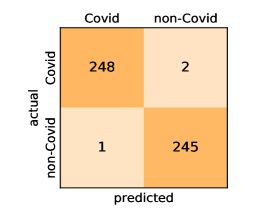

Here, we present and discuss the obtained results for detecting COVID-19 on the considered CT image datasets with different deep networks. We report the quantitative results along with the confusion matrices for every single architecture of the adopted networks.

Our models achieve fairly good performance compared with the recently published work using the exact network architectures. This can bet attributed to a better optimization of our models and the effectiveness of our fine-tuning strategy using custom-sized inputs determined specifically for each architecture. Here, we see that DenseNet201 outperforms all other architectures. The model achieves average accuracy and sensitivity scores of and , respectively. It also identifies all COVID-19 images with only four images, on the average, are falsely predicted as Non-COVID-19. DenseNet169 achieves the second best average accuracy of and a very high sensitivity identical to the best model. The DenseNet121 and Xception models have nearly identical results for all evaluation metrics. We observe that small-sized networks such as ResNet18 achieves comparable results with other deeper models. The SqueezeNet and ShuffleNet models perform at a similar level of accuracy. The variants of the ResNeXt models have comparable results and perform as good as the different ResNet variants. A detailed analysis on the class-wise results for individual models is presented in the confusion matrices in Figure 10.